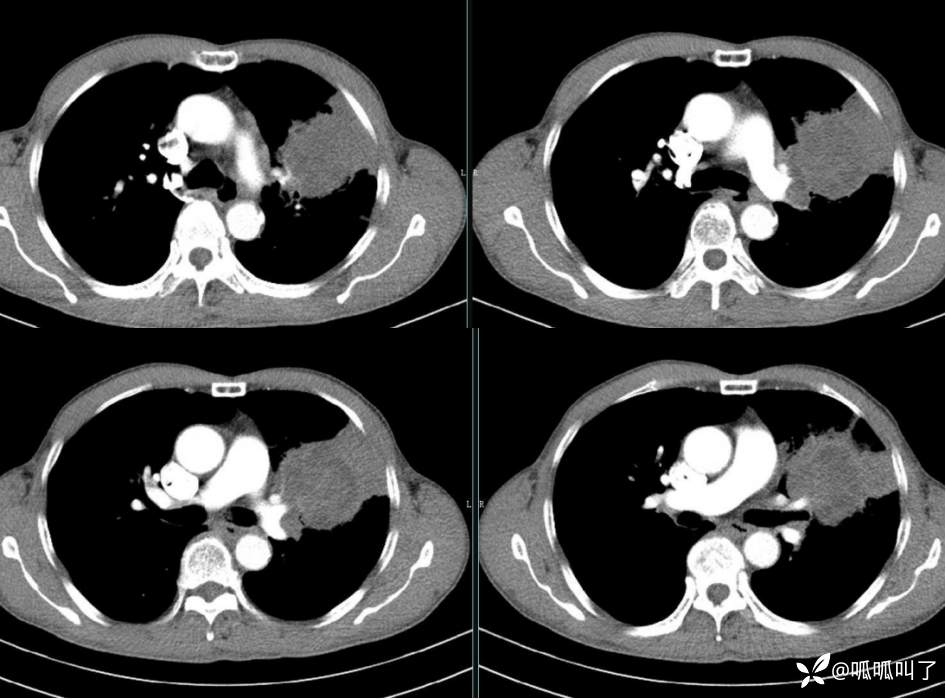

胸部CT平扫和增强: